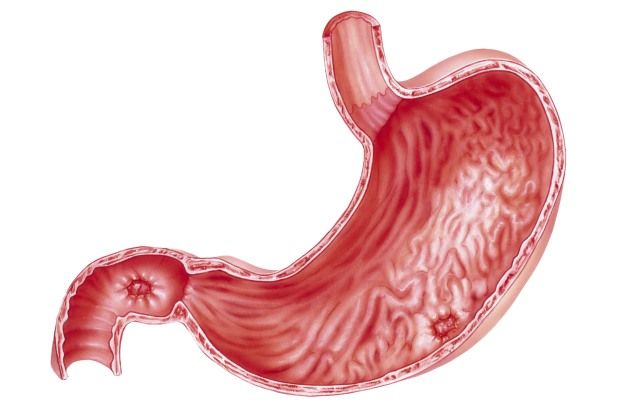

2. Viêm loét dạ dày tá tràng

Viêm loét dạ dày căn bệnh dạ dày gây tổn thương viêm và loét trên niêm mạc dạ dày hoặc tá tràng (phần đầu của ruột non), tổn thương xảy ra khi lớp niêm mạc của dạ dày hay tá tràng bị bào mòn và các lớp bên dưới thành dạ dày hay thành ruột sẽ bị lộ ra. Vết loét ở tá tràng chiếm 95%, vết loét ở dạ dày chiếm 60%, trong đó vết loét ở bờ cong nhỏ dạ dày chiếm 25% các trường hợp.

- Tuỳ vào vị trí viêm loét khác nhau mà bệnh sẽ được chẩn đoán và xác định với nhiều tên gọi khác như viêm dạ dày, loét hang vị, loét tiền môn vị, viêm loét tá tràng, viêm tâm vị,…

Viêm hang vị dạ dày là tình trạng tổn thương lớp niêm mạc dạ dày ở vị trí gần cuối dạ dày, trước phần môn vị.

- Dạ dày được chia thành nhiều vị trí bắt đầu từ tâm vị, phình vị, bờ cong lớn, thân vị, bờ cong nhỏ sau đó mới đến hang vị và vị trí cuối cùng chính là môn vị.